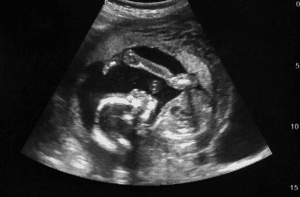

Fetal Anomaly Scan (18-24 weeks): Often performed between the 19 and 22 weeks of pregnancy, this scan ensures that all organs and body parts of the fetus look normal. The position of the placenta and blood flow of the fetus are also assessed for the management of the pregnant woman during pregnancy.

Fourth month fetal sonogram

Growth Scan or Fetal Well-Being Scan (24-42 weeks): These scans assess the size and health of the fetus. Head, abdominal, and thigh measurements aid in determining the weight of the fetus and the volume of amniotic fluid. Umbilical cord blood flow is assessed and fetal positioning towards the delivery is observed for better birth preparation. Subsequent scans may be done at 4-week intervals if results are not suggestive of earlier evaluations.